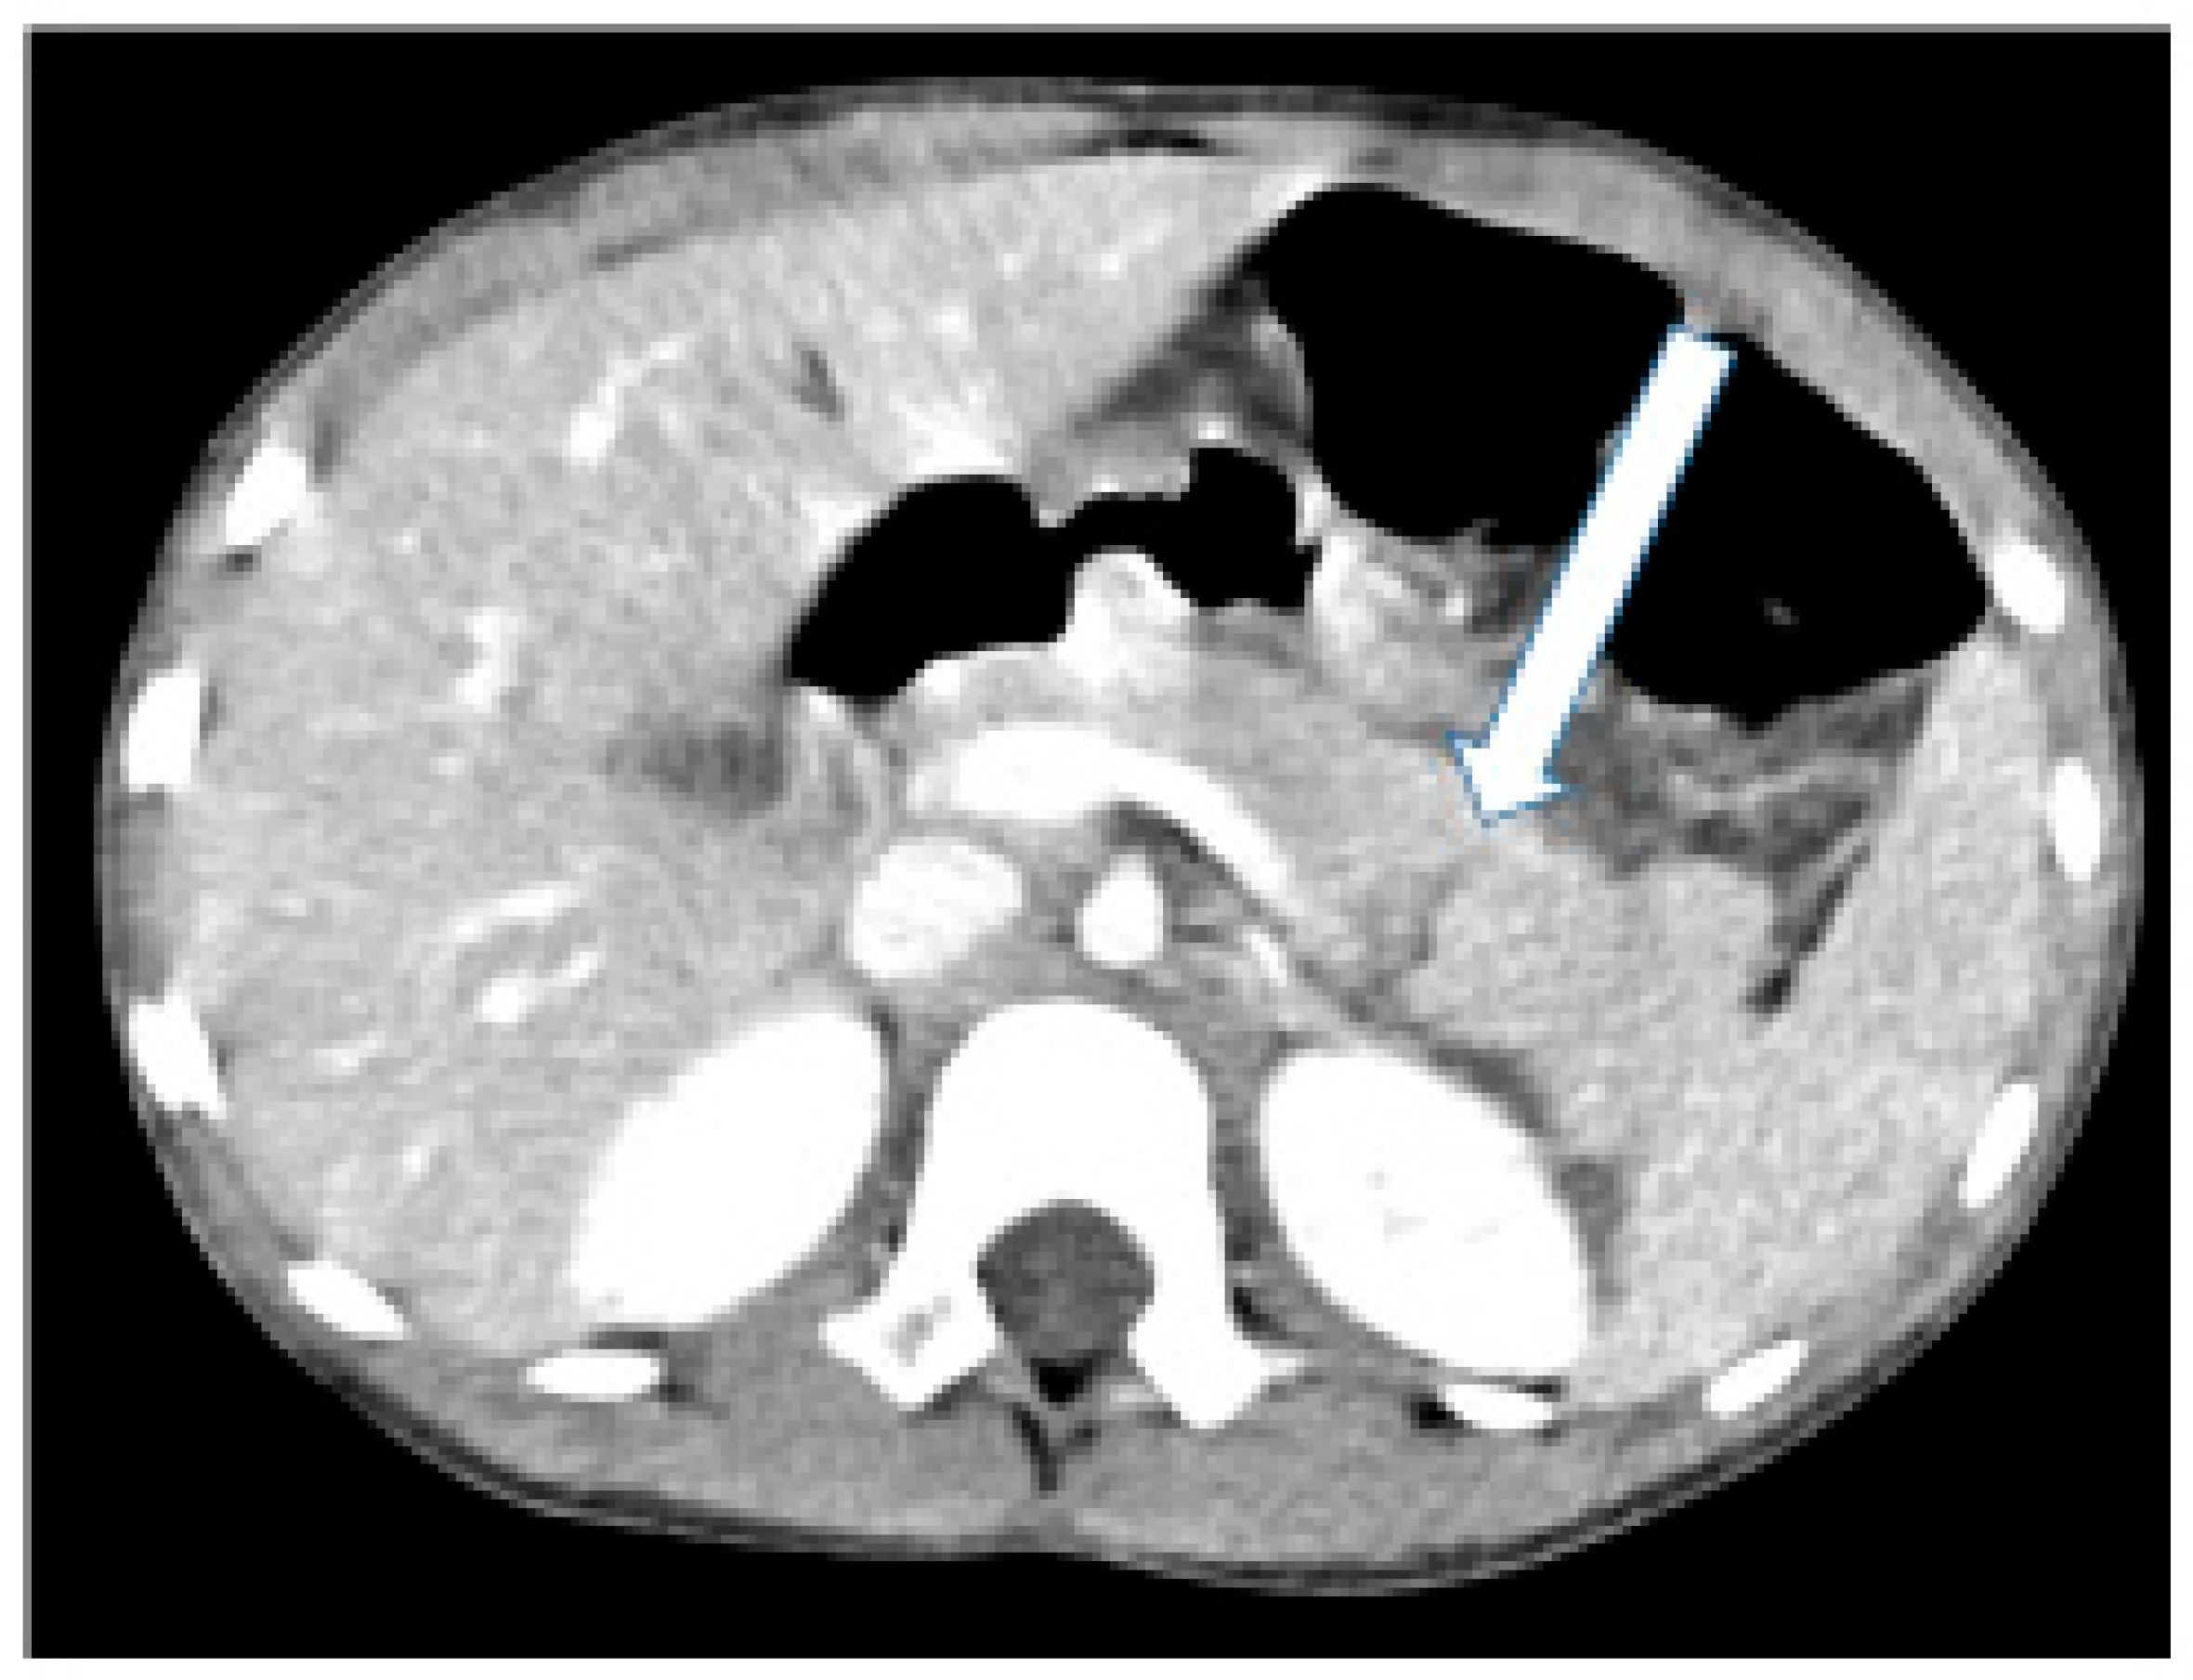

A 6-year-old girl arrived at the Pediatric Emergency Department 24 h after she had fallen on her bicycle handlebar and experienced discomfort in her left upper abdomen. Her medical history revealed no prior conditions or medications. The PED assessment by the medical team followed the advanced trauma life support (ATLS) protocol. Her airway was clear, and breathing was normal. She had tachycardia (heart rate: 140 bpm), but good capillary refill and normal perfusion. Blood pressure was normal for her age. She rated her pain at 4/10 on a visual analogue scale. There was a reddish bruise between her lower left chest and upper left abdomen, accompanied by local mild tenderness. She displayed no neurological deficits. The focused assessment with sonography in trauma (FAST) examination revealed a small amount of fluid in the suprapubic area. A contrast-enhanced computerized tomographic (CT) scan revealed a laceration in the distal pancreas, with limited visibility of the main pancreatic duct (MPD) (Figure 1).

Figure 1. Abdominal computed tomography scan demonstrating a pancreatic injury to the left of the superior mesenteric vein (arrow).